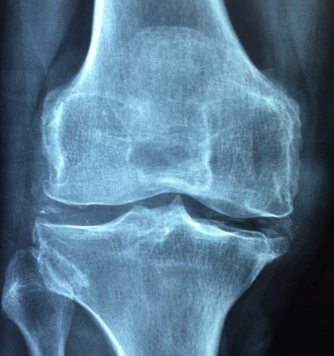

무릎 앞쪽에서 발생하는 통증으로는 슬개대퇴증후군, 슬개건염, 연골연화증과 같은 것들이 대표적인 원인 입니다. 무릎 앞쪽의 구조는 무릎의 뼈중 뚜껑뼈인 슬개골을 중심으로 상부에는 대퇴사두근건과 아래쪽으로는 슬개건이라고하는 힘줄 부분이 있습니다. 또한 무릎관절과 양쪽 골반 사이 부분에 위치해 허벅지를 지탱해 주는 넙다리뼈라고 불리는 대퇴골이 자리하고 있습니다.

슬개대퇴증후군은 슬개골과 대퇴골의 밀접한 관련성에서 시작되는 질환입니다. 슬개골은 무릎을 굽히거나 펼 때 대퇴골의 여러 면과 닿아 있습니다. 만약 이 두 뼈가 잘 맞물리지 않은 경우에는 ‘찌릿찌릿’ 아픈 통증이 느껴집니다. 뼈가 엇갈리게 닿게되면서, 그리고 주위의 인대도 다른 방향으로 당겨 통증을 유발시키기 때문입니다. 산을 내려오거나, 쪼그려 앉기, 무릎 꿇은 자세 등 무릎에 부하를 많이 주는 신체 동작의 경우에 증상이 나타납니다.

무릎 연골연화증은 무릎뼈를 감싸고 있는 연골이 부드러워지거나 약해지면서 탄력을 잃고 충격을 이기지 못하고 손상되는 질환을 말합니다. 초기 당시에는 단순한 염증으로 시작되는 질환이지만 점차 연골 전체 부분에 균열로 이어져 뒤 손상 단계로 진행돼 무릎의 기능을 떨어뜨리게 됩니다.